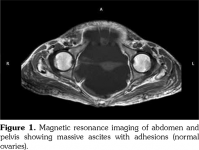

We performed extended investigations that showed normal blood albumin level. Tumor markers were significant only for an elevated serum cancer antigen 125 (CA-125) (80 U/L normal <35). Work-up for TB was negative including adenosine deaminase and polymerase chain reaction in ascitic sampling. Cytology was negative for malignant cells. We conducted computed tomography scan for the chest, abdomen and pelvis with contrast showing massive ascites with ill-defined omental thickening related to the anterior abdominal wall. A cystic lesion was seen at perineal region, minimal bilateral pleural effusion and massive abdominal ascites. Laparotomy and biopsy were performed revealing fat necrosis. Subsequently, magnetic resonance imaging of the abdomen and pelvis was conducted but it was insignificant apart from massive ascites with adhesions. No ovarian masses were observed (Figure 1). In lower perineal region, herniating peritoneal sac was noted containing ascitic fluid representing peritoneocele (Figure 2).